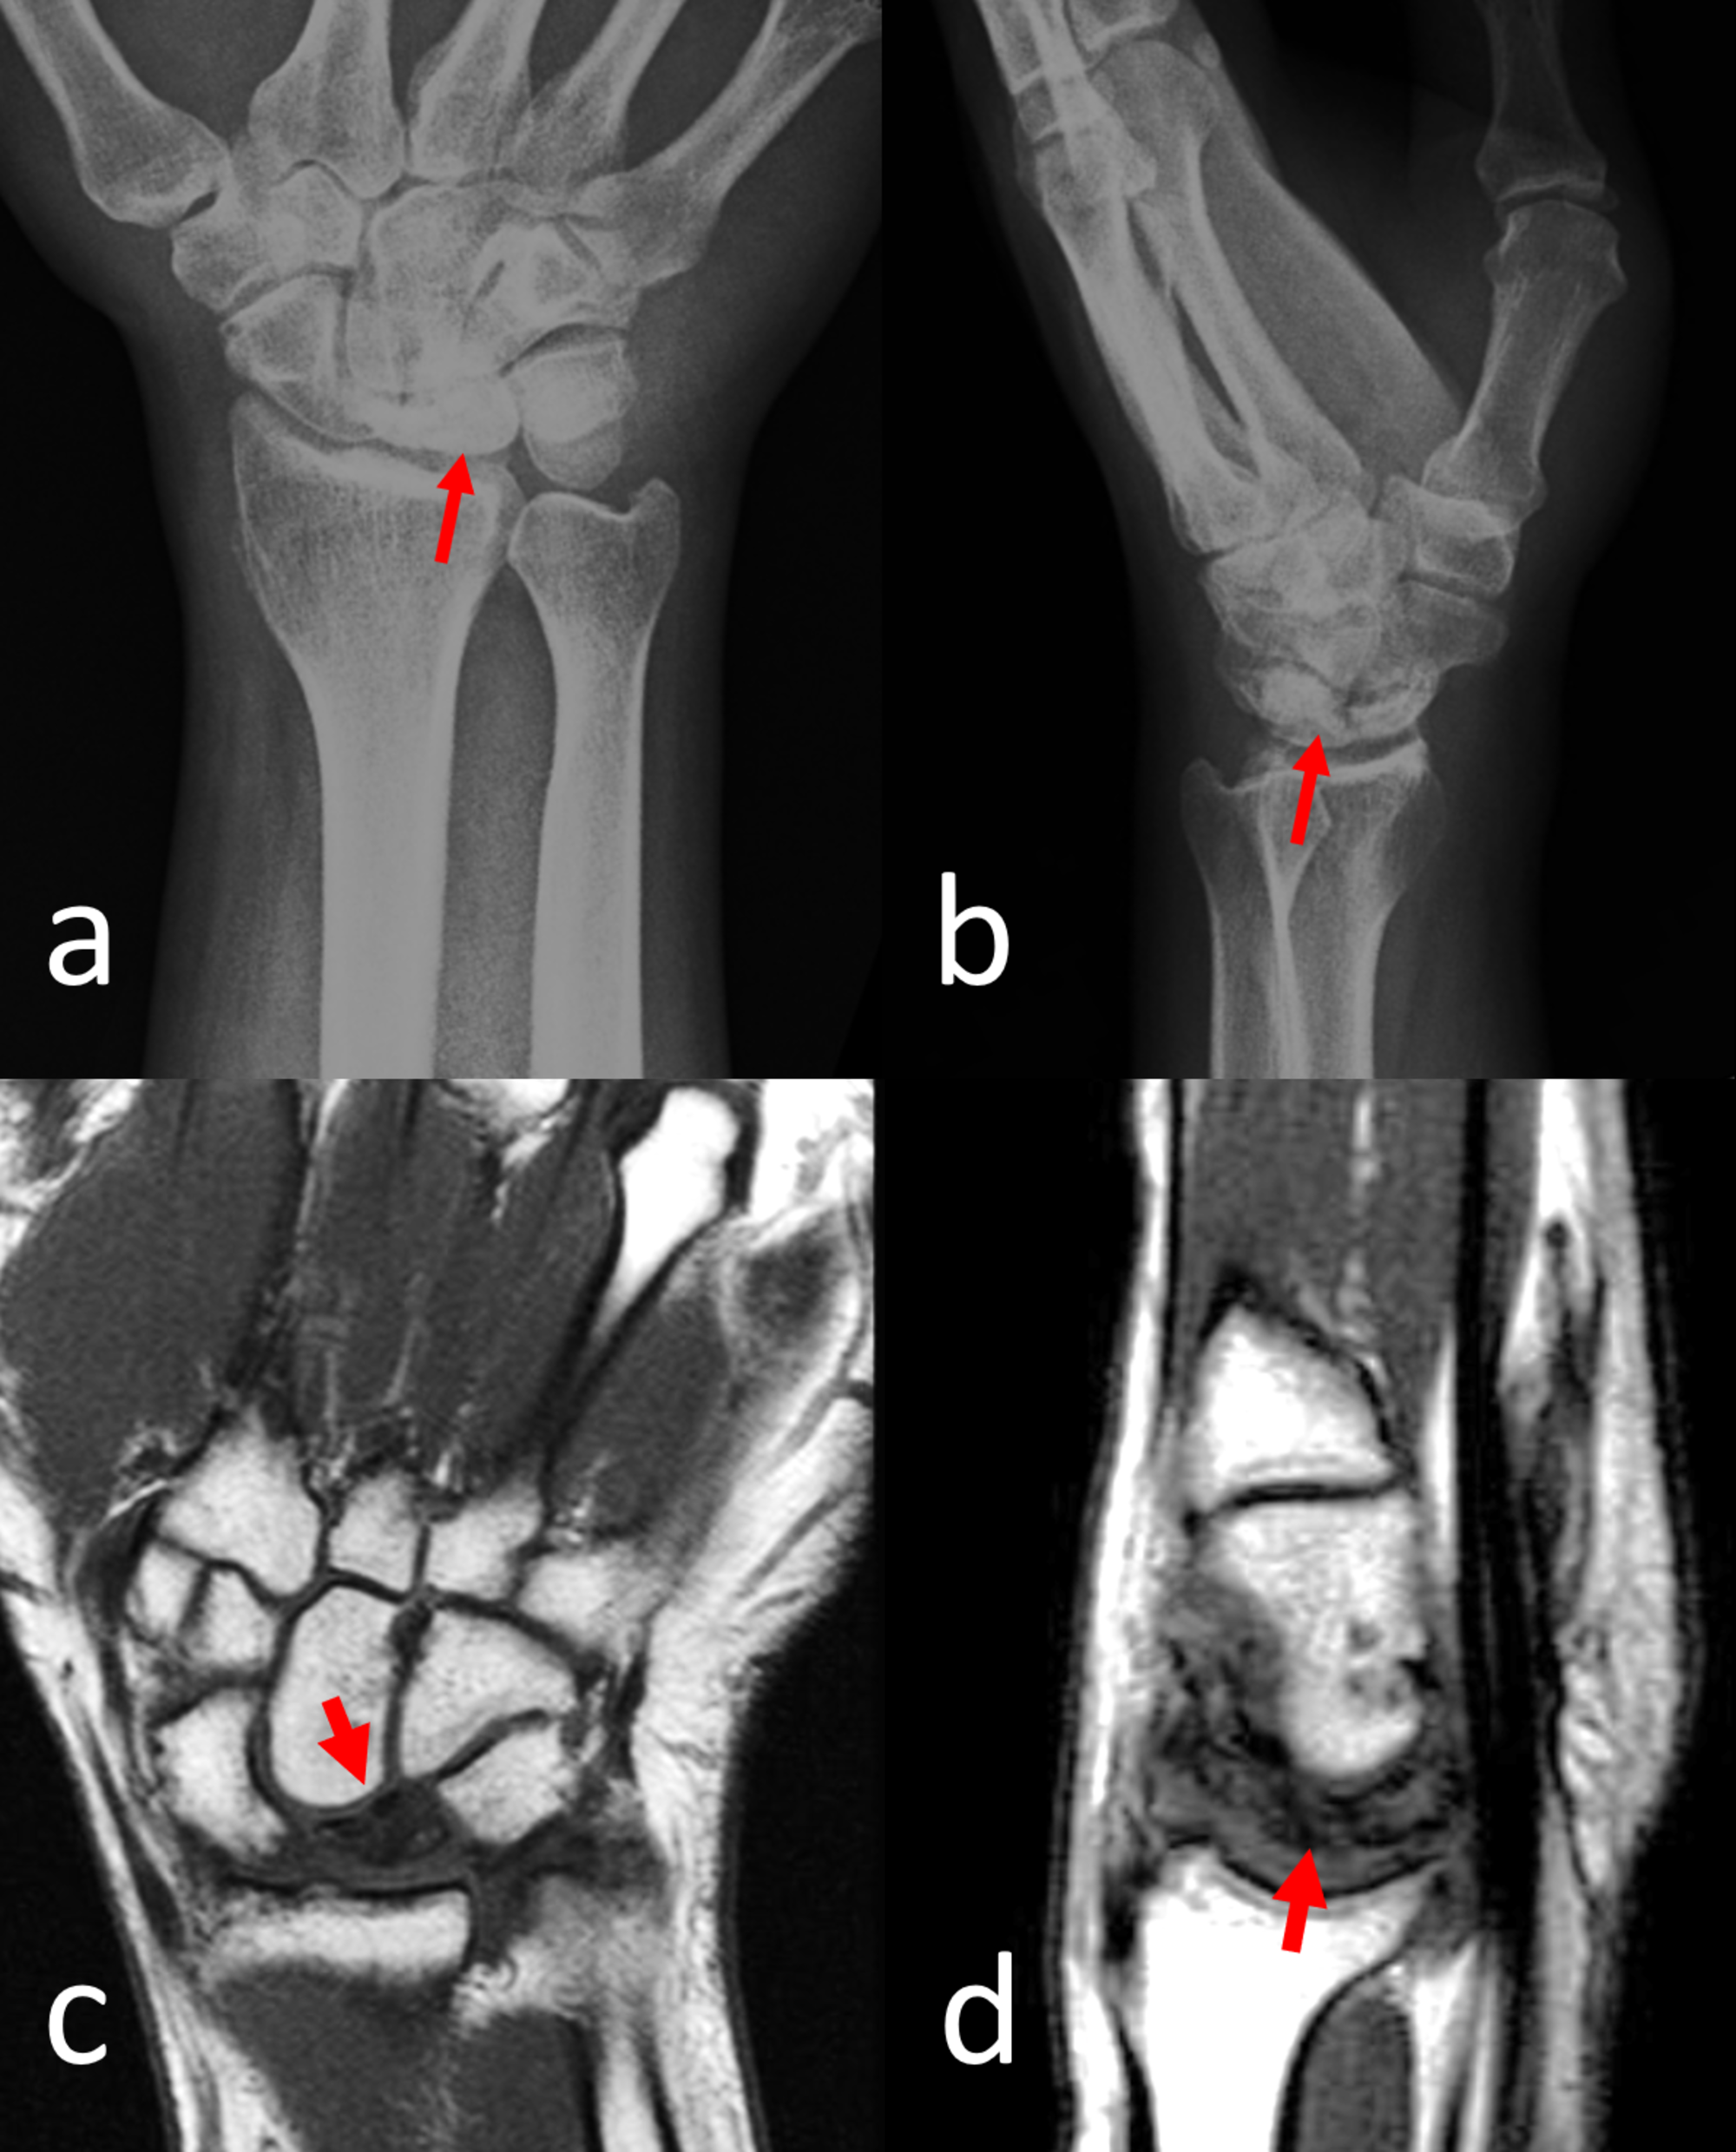

Early scapholunate advanced collapse treated with scaphoidectomy and …

SLAC wrist arthritis – John Erickson, MD

SLAC Wrist|Causes|Symptoms|Staging|Treatment|Surgery|Prevention

( A ) Anteroposterior ( left ) and scaphoid-view ( right ) radiographs …

Radiograph of non-union in four-corner fusion (anteroposte- rior …

SNAC (Scaphoid Nonunion Advanced Collapse) – Hand – Orthobullets

A. The plain radiograph of the right wrist demonstrating type III …